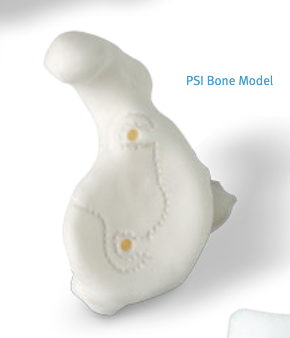

Patient specific instrumentation

Zimmer PSI Trabecular metal rTSA

Zimmer Signature One Surgical technique PDF